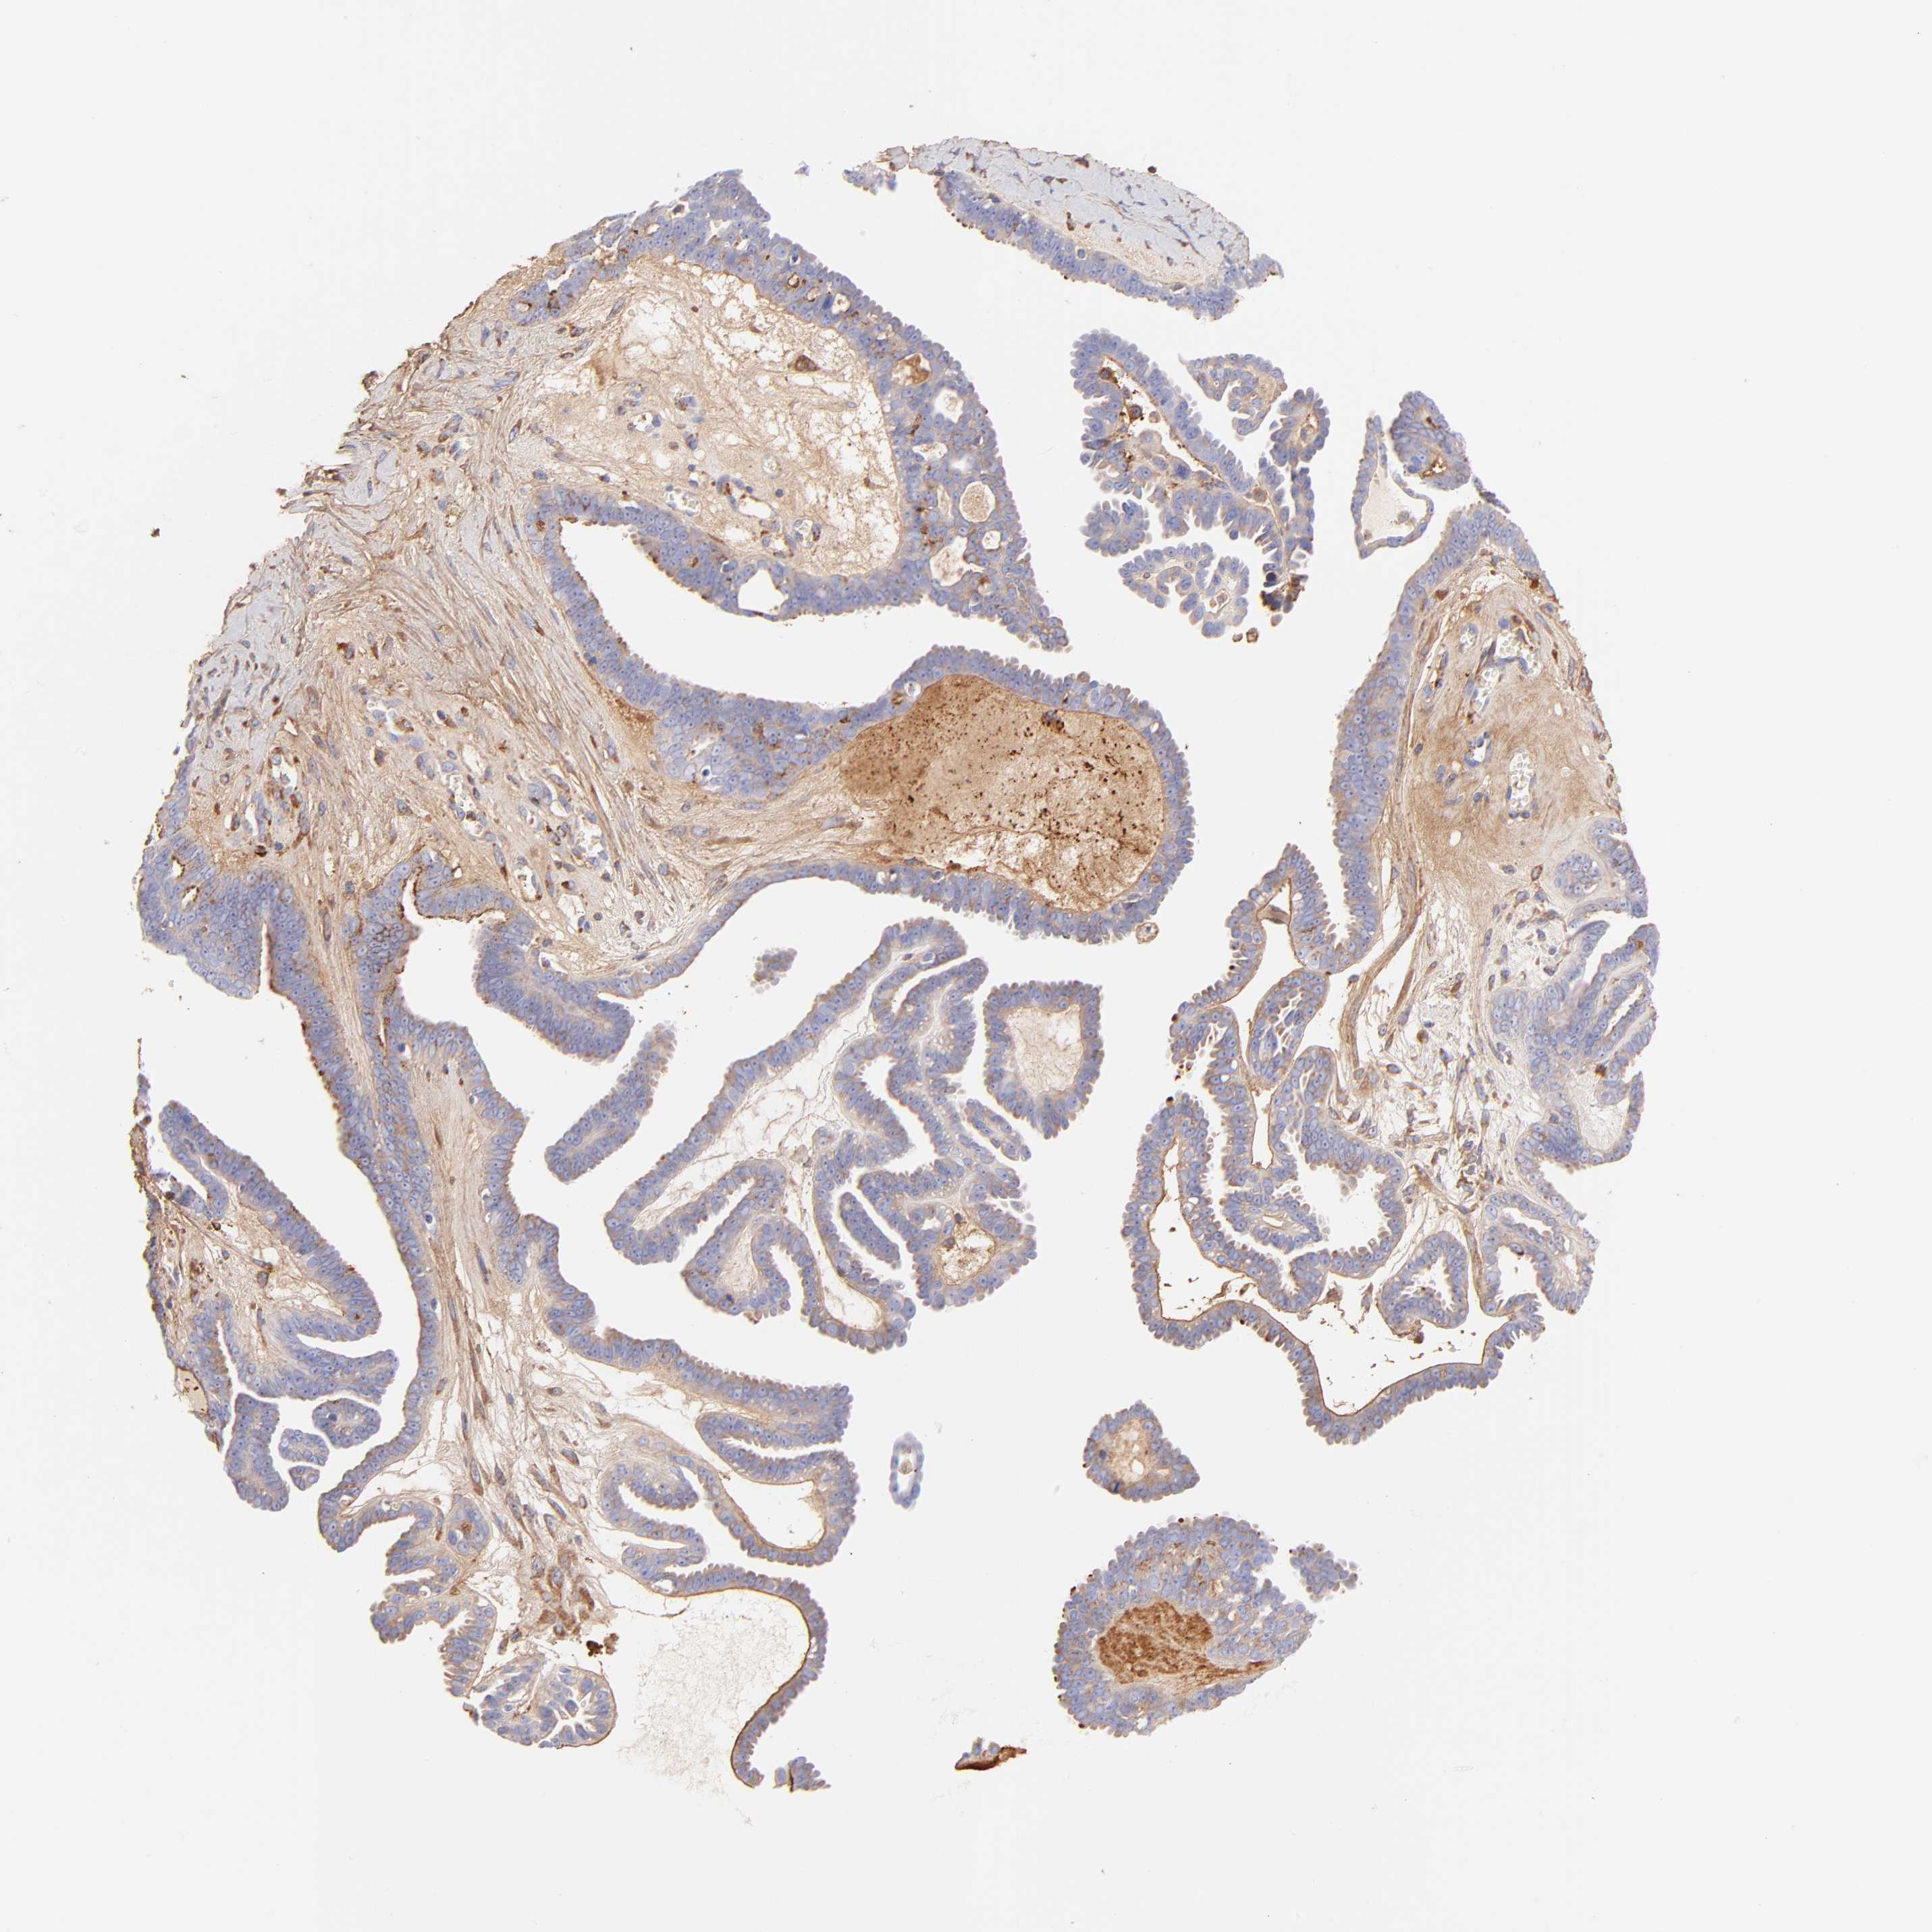

OVARIAN CANCER - Protein expressioni

A mouse-over function shows sample information and annotation data. Click on an image to view it in a full screen mode. Samples can be filtered based on level of antibody staining by selecting one or several of the following categories: high, medium, low and not detected. The assay and annotation is described here.

Note that samples used for immunohistochemistry by the Human Protein Atlas do not correspond to samples in the TCGA dataset.

Antibody stainingi

Antibody staining in the annotated cell types in the current human tissue is reported as not detected, low, medium, or high, based on conventional immunohistochemistry profiling in selected tissues. This score is based on the combination of the staining intensity and fraction of stained cells.

Each image is clickable and will lead to virtual microscopy that enables deeper exploration of all samples and also displays staining intensity scores, fraction scores and subcellular localization as well as patient and tissue information for each sample.

Antibody HPA003157

Antibody CAB003678

Carcinoma, endometroid

Cystadenocarcinoma, serous, NOS

Cystadenocarcinoma, mucinous, NOS